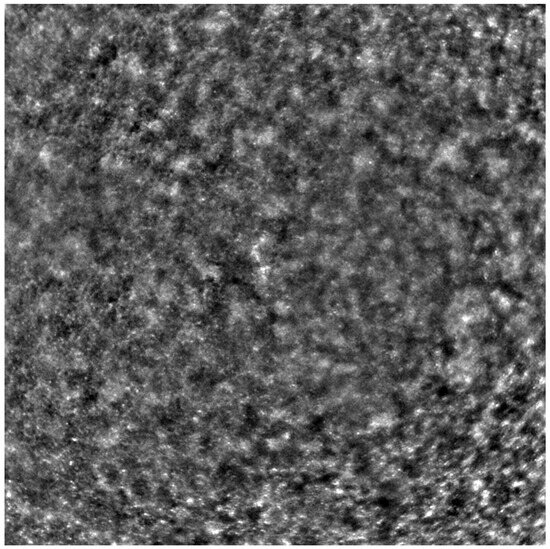

Adaptive optics retinal images depicting a healthy eye, CD, CRD, and STGD are presented in Figure 1, Figure 2, Figure 3 and Figure 4.

Figure 1 depicts the photoreceptor mosaic in a healthy eye. The image is taken paracentrally (2 ° superiorly) due to the limited ability of foveal image acquisition by Rtx™ [17]. By changing the focus point, the quality of an acquired image provides the assessment of photoreceptor parameters in parafoveal cones. The aberration and noise found in Figure 2, Figure 3 and Figure 4 are considered to be the result of poor fixation in eyes with impaired central vision in the course of macular disease. This issue has been addressed in our study. The assessment of factors predisposing for obtaining inadequate image quality was taken into consideration further in this article.

Cone mosaic disruption is an abnormality typical of IRDs. The cone and rod spacing is increased in IRDs compared to healthy retinas [18]. Additionally, poor image quality, likely resulting from inadequate fixation in eyes with low visual acuity, is a problem that, in some cases, makes image acquisition impossible [19,20]. In STGD, as well as in other IRDs, the “dark spaces” depicting areas of disrupted cone structure and abnormal cone reflectance have been described [21,22].

Figure 4. An adaptive optics image of the photoreceptors of the eye with Stargardt disease (Rtx1™; Imagine Eyes, France). The photoreceptor mosaic is disrupted, note the appearance “dark spaces” among the cone mosaic in various regions of the picture.